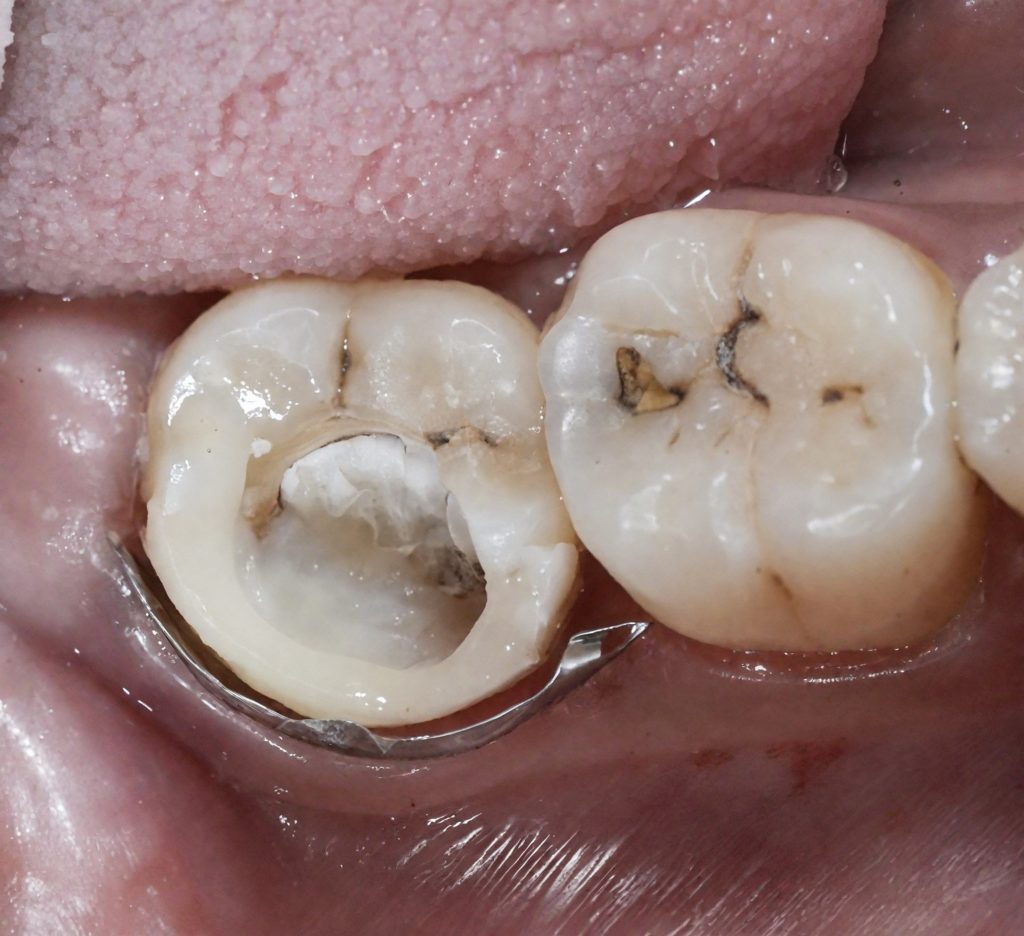

2 Isolation and Access

Full rubber-dam isolation was achieved using a pink dam for enhanced visibility (Fig 3). Conservative access under the dental microscope preserved pericervical dentin.

3️⃣ Rubber-dam isolation (pink dam)

4️⃣ Access refinement under scope